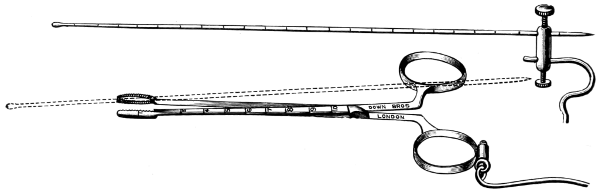

| 89 A and B. Sheen’s bullet probe, forceps, and telephone bullet-detector[xi] | 302, 303 |

| 53. A basic fracture with laceration of both carotid arteries | 148 |